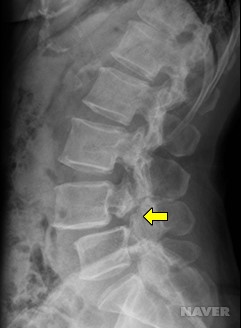

척추 분리증이 진행되면

척추가 바로 아래 척추에 대해

앞으로 이동하는 척추 전방 전위증이 발생할 수 있다.

가장 흔한 경우로 5번 요추가

바로 아래에 위치한 1번 천추에 대해

미끄러지듯이 앞쪽으로 빠지게 된다.

소아에서는 척추 분리증이

척추 전방 전위증으로 진행하지 않는지

1년마다 X선을 촬영하여 비교해보는 것이 좋다.